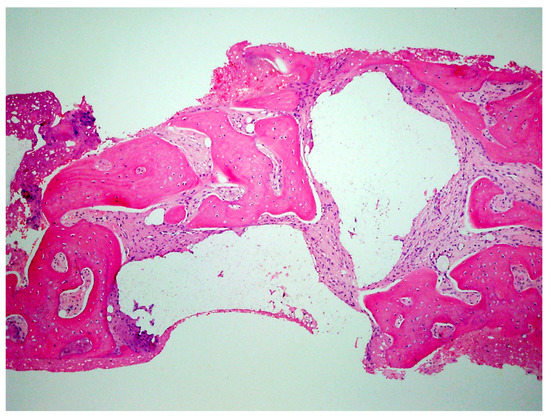

Figure 19.

Histology of the core sample obtained following 10 weeks of graft site healing demonstrating well preserved reactive (woven) trabecular bone with intertrabecular tissue composed of uniformly collagen-rich myofibroblastic tissue and 60% of the core consisting of bone.

A critical question is about what happens histologically to the graft and at what stage during healing. For example, when delayed socket grafting was performed at a site where a large defect was present following extraction (Figure 18, left), a healing period of 3 weeks post-extraction was needed, allowing primary closure post-graft. This gives us more predictability and simpler surgery, plus two attempts to clean the site. EthOss graft material was placed into the socket (Figure 18, middle) and primary closure with the flap was achieved and secured with sutures (Figure 18, right). Intraoral physical exam and radiographic measurement showed all sites to have regenerated vertically 3–6 mm and horizontally 4–6 mm with new host bone allowing for successful placement of the implants. A core sample was obtained from one case to confirm the series to be in line with earlier findings. Histology was performed by core biopsy at 10 weeks following graft placement and demonstrated well-preserved reactive (woven) trabecular bone with intertrabecular tissue composed of uniformly collagen-rich myofibroblastic tissue and 60% of the core consisting of bone (Figure 19).